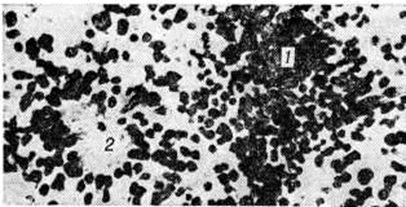

Рис. 2.

Микропрепарат симпатогониомы: видны скопление гиперхромных лимфоцитоподобных клеток (1) и псевдорозетка (2); окраска гематоксилин-эозином; × 450.

Симпатогониома — наиболее злокачественная, незрелая, примитивная опухоль; встречается у новорожденных и в раннем детском возрасте. Опухолевые клетки — со скудной цитоплазмой и округлым темным ядром, напоминающим лимфоцит. Иногда встречаются псевдорозетки (рисунок 2). Эти клетки происходят из примитивных клеток — симпатогоний, отсюда термин «симпатогониома».